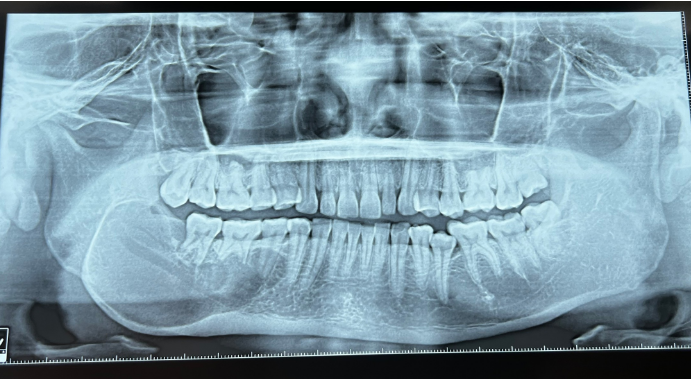

Bệnh nhân nam N.Q.N (1995, Quảng Ngãi) phát hiện khối u ở xương hàm dưới cách đây 6 năm nhưng ngừng điều trị sau thời gian đầu theo dõi. Gần đây, tình trạng sưng phồng gia tăng, bệnh nhân đến Bệnh viện Quân y 175 trong tình trạng hàm dưới sưng nề, niêm mạc viêm đỏ nhẹ, đau ít. Kết quả chẩn đoán hình ảnh cho thấy khối u phá hủy xương từ răng số 44 đến ngành lên hàm dưới phải.